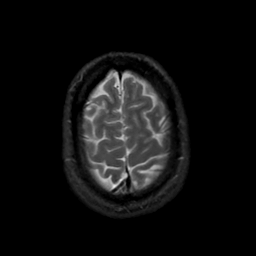

MR Study #22, December 1, 1991 -- Slice #43

[Home][Help][Clinical][Tour 1][Tour 2] Slice 43